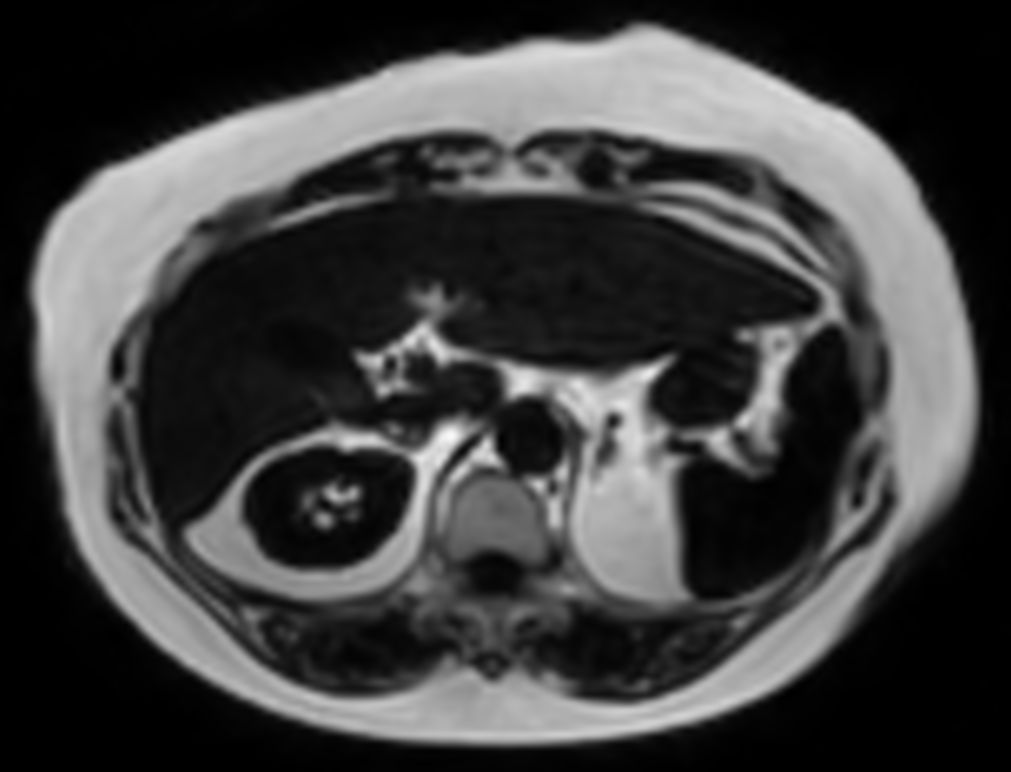

mDIXON XD Quant (Water only)

mDIXON XD Quant (Fat only)

mDIXON XD Quant (Fat Fraction Map)

mDIXON XD Quant (T2* Map)